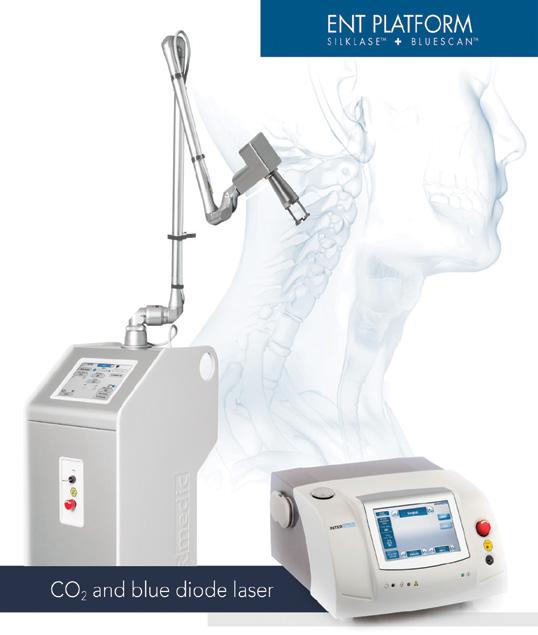

Aveți preocupări deosebite în ceea ce priveste microchirurgia laringiană în suspensie,

fonochirurgie, chirurgia LASER, chirurgia cu radiofrecvență, chirurgia laringiană oncologică cu viză funcțională care definesc imaginea omului de ştiință şi practician.